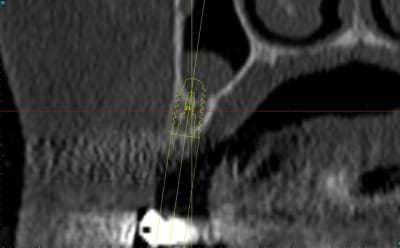

3:

de nouveau ostéotome "lame" angulé

Ostéotome droit, plus étroit que le premier.

4:

évolution

Tatum D1